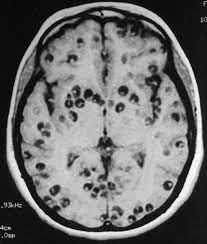

El caso de un joven atendido por fuertes dolores de cabeza y convulsiones reveló una enfermedad conocida como neurocisticercosis, provocada por larvas del parásito Taenia solium.

Estas larvas se alojan en el cerebro, causando inflamación, daño neuronal y, en casos graves, convulsiones o la muerte.